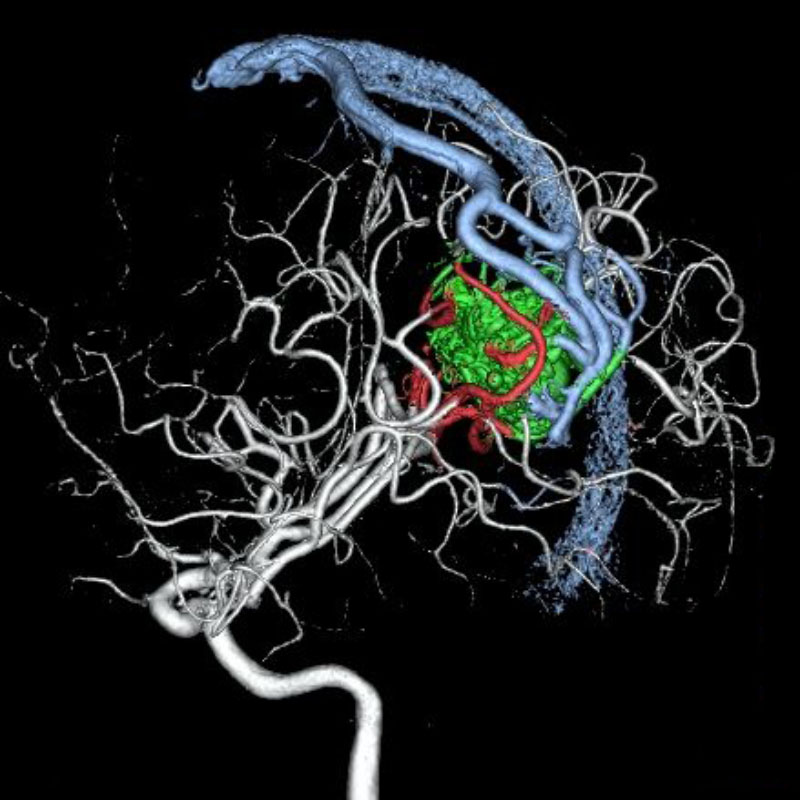

脳血管撮影

手術前

手術後

手術中

手術写真